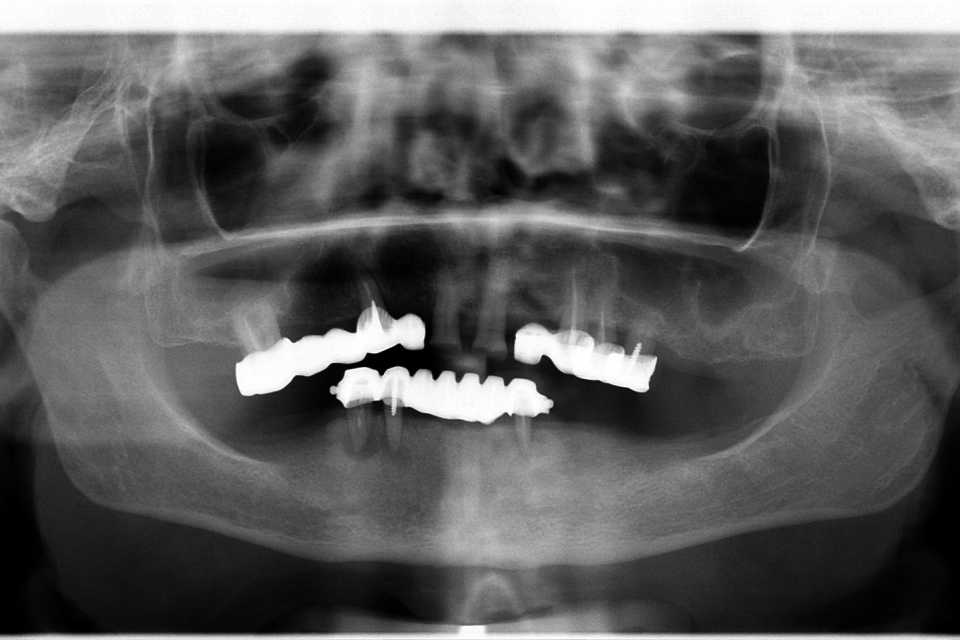

Pacienta, în vârstă de 65 de ani, se prezintă în cabinet acuzând dureri în timpul masticației, mobilitate dentară, halitoză și un aspect inestetic.

Planul de tratament a inclus extracția dinților parodontotici la nivelul mandibulei și inserarea a 5 implanturi dentare Mega-Gen AnyRidge cu conexiune multiunit, urmată de protezarea acestora cu o lucrare fixă, înșurubabilă, din ceramică pe suport de zirconiu.

La nivelul maxilarului, s-au efectuat extracțiile dinților parodontotici, tratamentul laser și chirurgical al leziunilor parodontale, urmate de reabilitarea protetică prin realizarea a două lucrări fixe din ceramică pe suport de zirconiu.